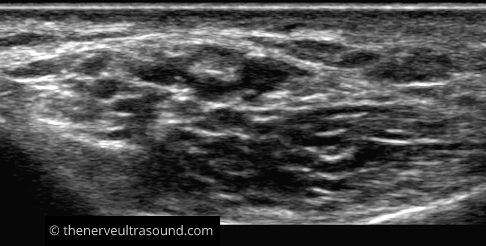

B: Tarsal tunnel

In or distal to the tarsal tunnel the tibial nerve divides into it terminal branches; the medial plantar (anterior) and the lateral plantar nerve.